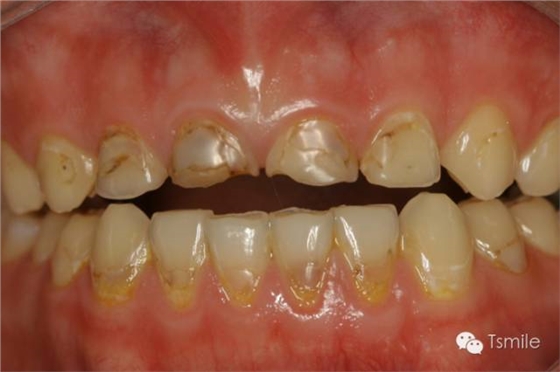

圖2: 前牙功能范圍受限導(dǎo)致的前牙重度磨耗 磨損是指在非下頜功能運(yùn)動(dòng)和副功能運(yùn)動(dòng)中,除牙齒以外的其它物體對(duì)牙齒表面機(jī)械摩擦而導(dǎo)致的牙齒表面硬組織缺損。 磨損患者一般有某種特殊的生活習(xí)慣或工作習(xí)慣,如不正確的刷牙方式、長(zhǎng)時(shí)間叼煙斗、咬指甲、咬鉛筆等生活和工作習(xí)慣。長(zhǎng)時(shí)間的不良習(xí)慣,這些煙斗、鉛筆、指甲等異物會(huì)對(duì)牙齒表面過(guò)度機(jī)械摩擦,導(dǎo)致牙齒表面硬組織缺損。

磨耗患者中還有一類(lèi)特殊的局限于上下前牙區(qū)的牙齒重度磨耗,表現(xiàn)為上前牙舌面、下前牙切端和唇面的重度磨耗。該類(lèi)患者常表現(xiàn)為一類(lèi)特殊的咬合類(lèi)型,重度深覆頜或者上前牙明顯舌傾,這種咬合類(lèi)型導(dǎo)致下頜前伸功能運(yùn)動(dòng)受限,從而導(dǎo)致前牙區(qū)重度的磨耗,可稱(chēng)為前牙功能范圍受限(restricted envelope of function)。